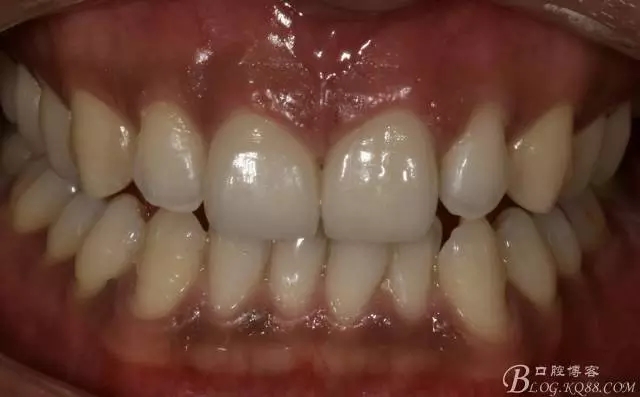

術后即刻照

640.webp (9).jpg

口內照

640.webp (10).jpg